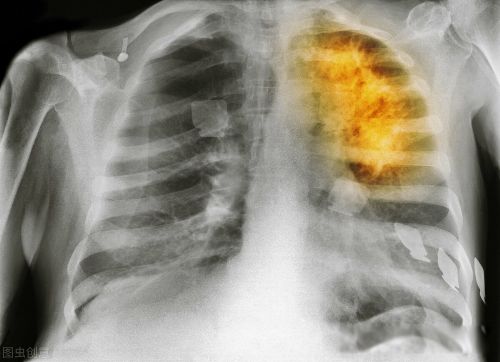

癌症是什么原因造成的?癌症是正常细胞在繁殖分裂过程中因受外在和内在致癌因素影响,致使细胞发生突变丶畸变形成癌细胞,即癌症。

二丶不良生活习惯。如吸烟、酗酒等不健康生活习惯。烟中的尼古丁易致肺癌。酗酒易诱发肝癌丶胰腺癌丶食道癌及胃癌肠癌。